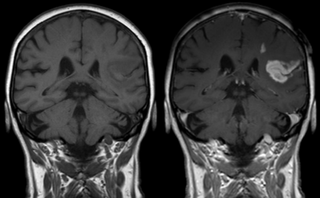

Effect of contrast agent on images: Defect of the

bloodbrain barrier after stroke shown in MRI.

T1-weighted images, left image without, right image

with contrast medium administration.